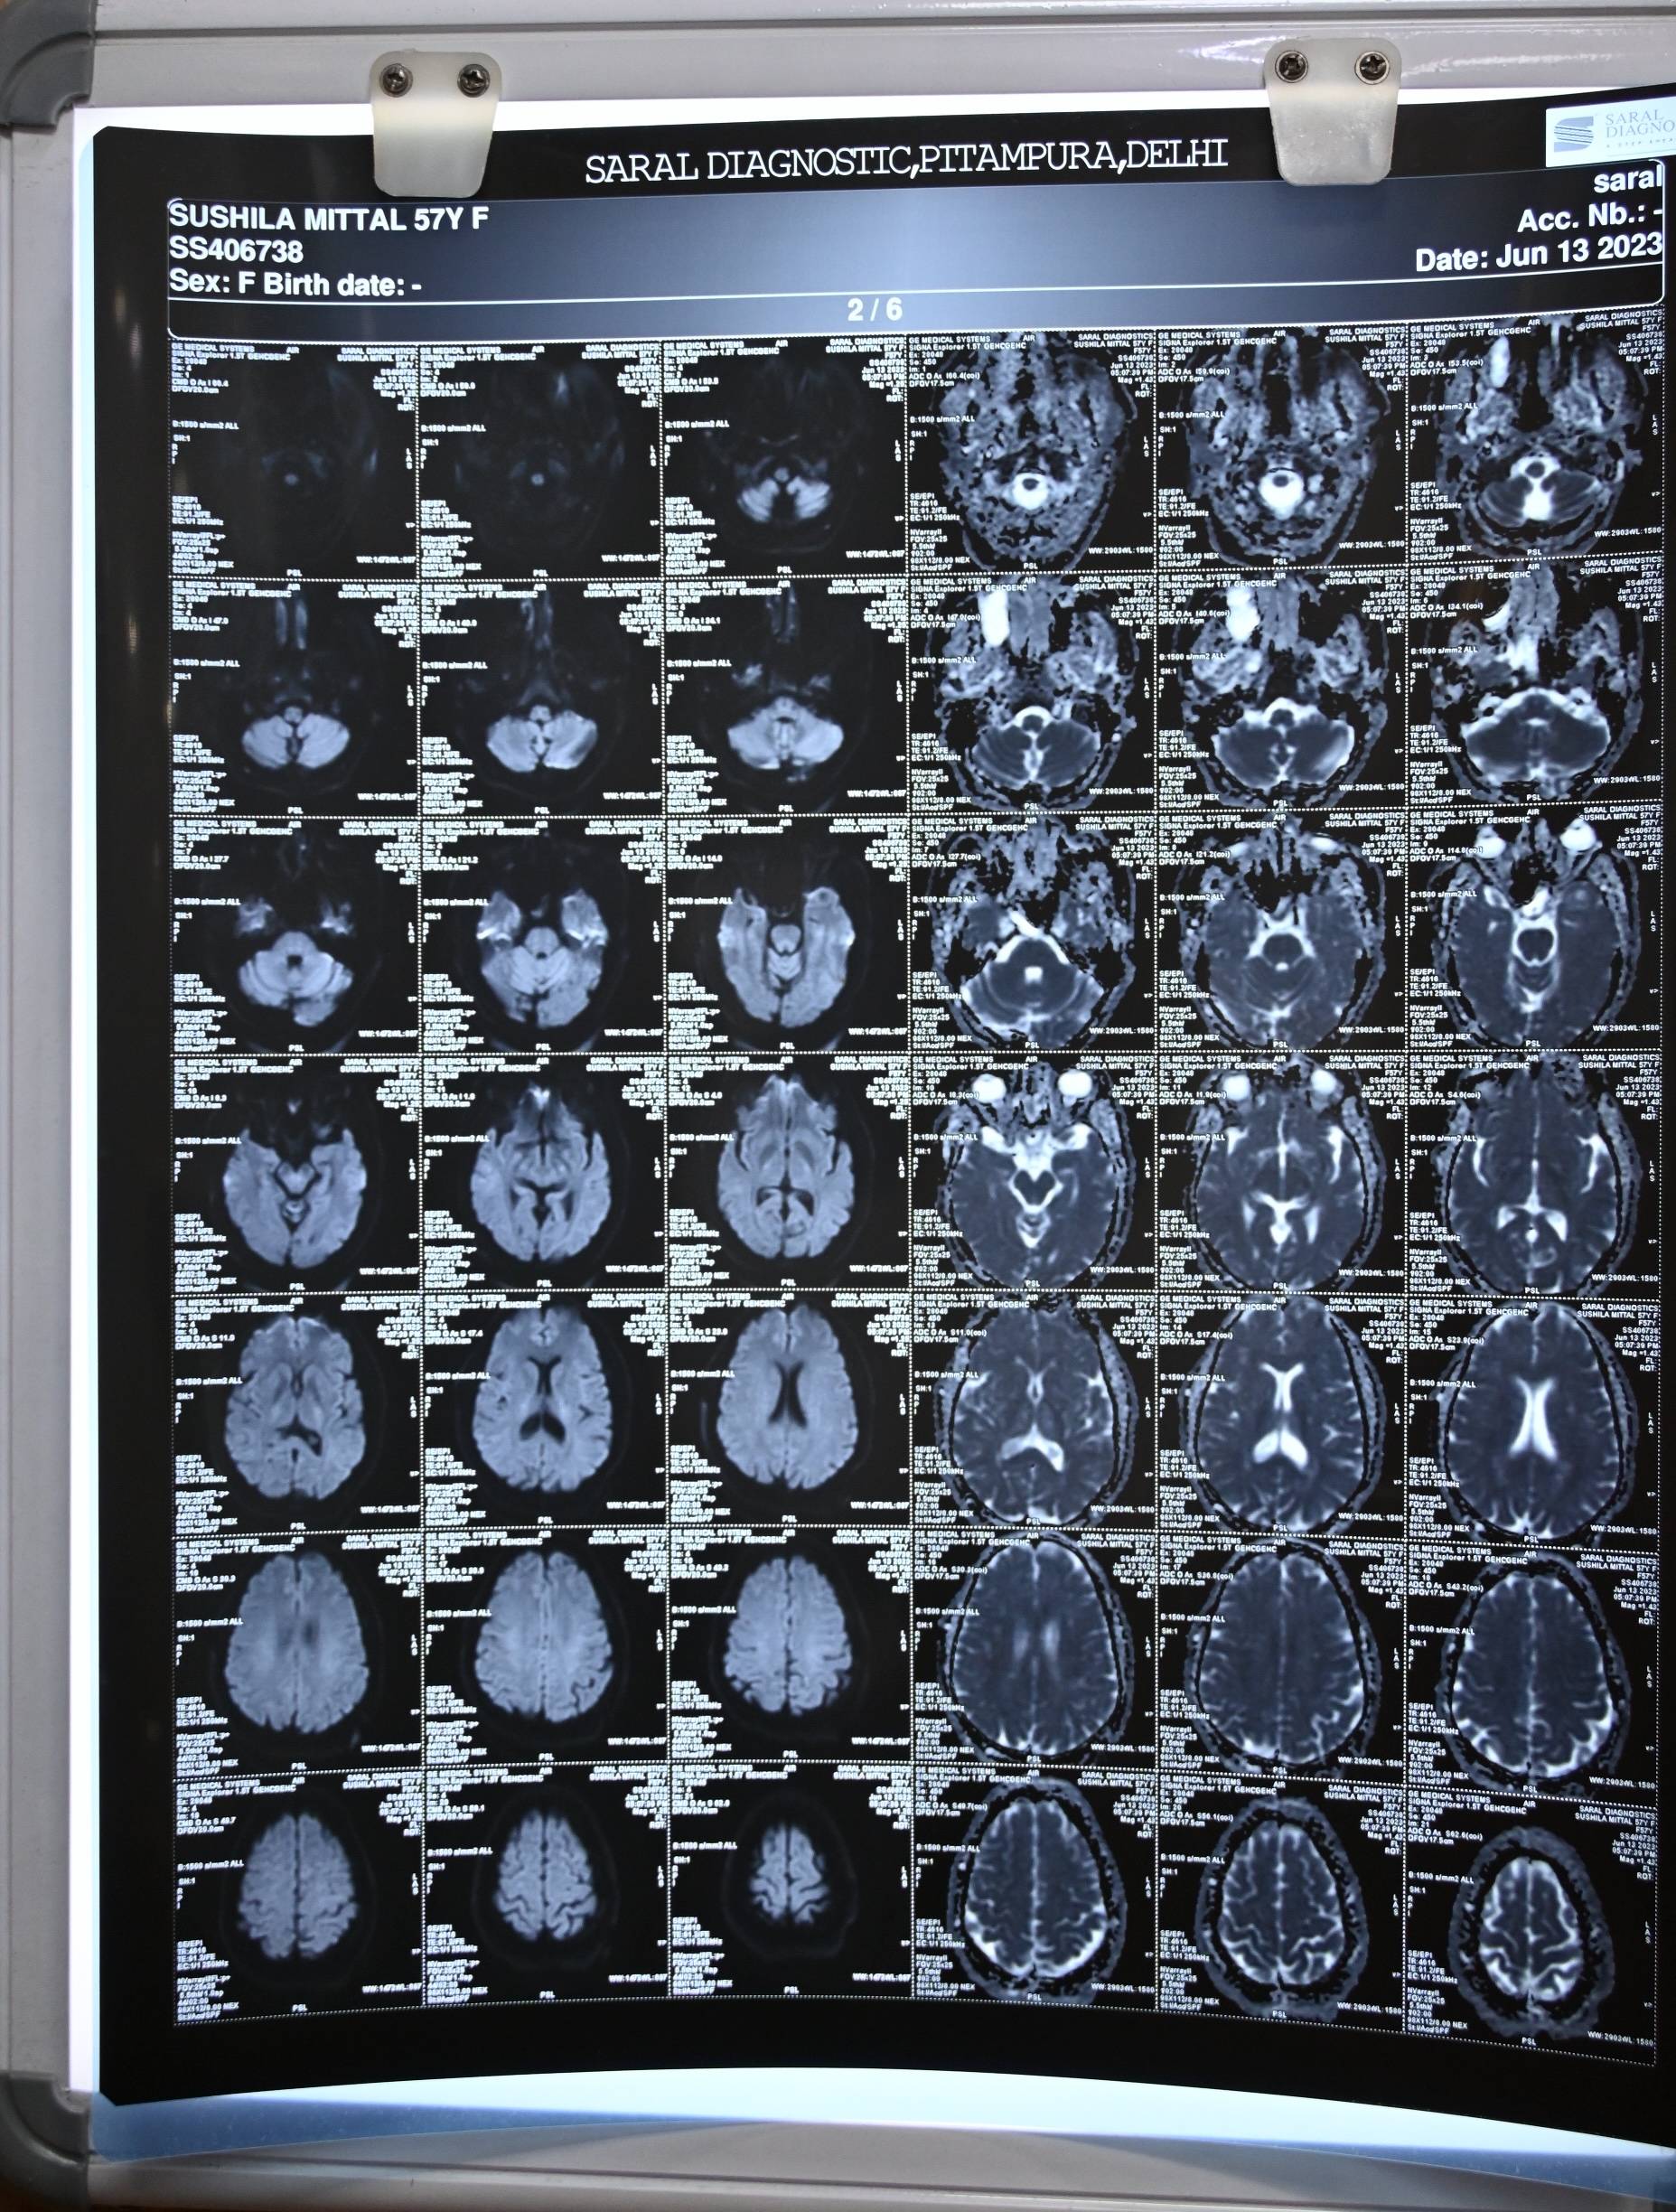

The patient was examined by an ENT surgeon and underwent an MR cisternography with contrast, which confirmed the clinical diagnosis. The report revealed two osseo-dural defects along the posterior wall of the lateral recess of the right sphenoid sinus, measuring approximately 3.1 mm and 2.4 mm, with small herniations of brain parenchyma measuring about 5 mm at both sites. The right sphenoid sinus and its lateral recess were filled with fluid revealing an isointense signal to CSF.